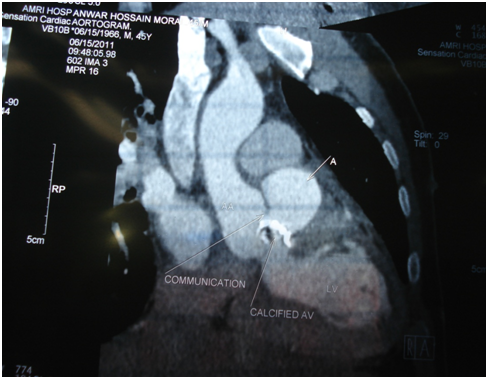

We presenting here a case of the patient with bicuspid aortic valve complicated with aneurysm of right sinus of valsalva. The aneurysm of sinus of valsalva was extracardiac and extending behind the main pulmonary artery and to the left. A 45years old Muslim male patient, carpenter by occupation was admitted with chief complaints of shortness of the breath and chest pain for 1 month. He was having orthopnoea and paroxysmal nocturnal dyspnoea and swelling of the feet. His vitals were stable with pulse rate 96/min, blood pressure 130/50mm Hg, and respiratory rate 14/min. On auscultation S1 was normal and S2 was soft with grade III/VI diastolic murmur in aortic area. Patient was properly investigated. ECG showed sinus rhythm and X-ray chest was showing cardiomegaly. Transthoracic echocardiography showed calcified bicuspid aortic valve, severe aortic regurgitation, grade II mitral regurgitation and that was appeared to be as dissecting flap in ascending aorta with 75% ejection fraction (Figure 1). Computed tomography chest was domne and it showed large pseudo-aneurysm of right sinus of Valsalva (Figures 2 & 3). Computed tomographic angiocardiography was done to define the lesion in the aorta accurately. Computed tomographic angiocardiography (Figures 4 & 5) revealed dysplastic aortic valve, para valvular aneurysmal sac communicating with aortic root as well as to left ventricle (? Pseudo-aneurysm). Routine investigations were done and patient was prepared for surgical intervention. Transoesophageal echocardiography was done in after induction of anaesthesia, which showed a large aneurysmal swelling behind the root of aorta. Conventional sternotomy was done. There were adhesions between pericardium and the heart. All adhesions were lysed. Aortotomy was done after institution of cardiopulmonary bypass. Bicuspid aortic valve and opening of the aneurysm were identified (Figure 6). Distorted, calcified aortic leaflets were excised and the opening of the aneurysm of sinus of valsalva was closed with Dacron patch from inside of the aorta (Figure 7). Aortic valve was replaced with sorin, bileaflet, mechanical valve, size 21 using interrupted ethibond, pladgeted sutures (Figure 8). Postoperative period was uneventful and patient was discharged on 7th postoperative day in good general condition. Patient is doing well in follow up visits.

Figure 2 CT scan.

Figure 3 CT scan.